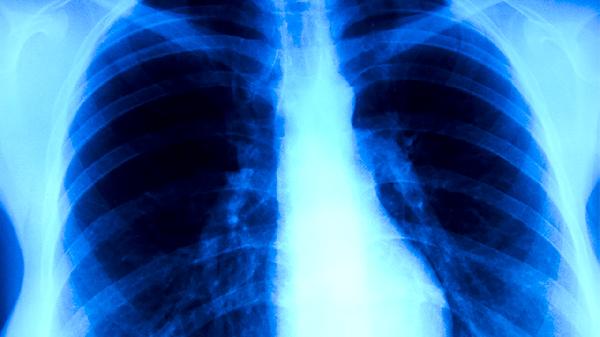

肺結(jié)核患者可通過(guò)高蛋白飲食、富含維生素的食物、適量碳水化合物、補(bǔ)鐵補(bǔ)鈣食物及易消化飲食等方式調(diào)整病情。肺結(jié)核是由結(jié)核分枝桿菌引起的慢性傳染病,合理飲食有助于增強(qiáng)免疫力、促進(jìn)病灶修復(fù)。